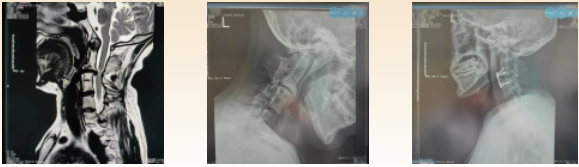

影检查提示:患者存在颈4/5椎间盘突出,相应节段脊髓受压变性,寰枕融合,颈2-4椎体及椎板、棘突融合,颈5-6椎体融合,颈5-6棘突隐裂,颈7椎体半椎畸形,颈7-胸1椎体融合,颈椎侧弯,左侧椎动脉发育缺如,椎枢关节失稳等一些列复杂的影像学表现。

颈椎融合畸形可继发生物力学改变,使邻近颈椎节段不稳定、韧带与小关节增生以及颈椎间盘退变,而这些都是导致脊髓神经压迫症状的直接原因。在颈椎不稳定性时,即使是轻微颈部外伤,都可能引起严重的脊髓损害导致四肢瘫甚至呼吸心跳骤停。这些都严重威胁患者的生命健康,且患者已经出现躯干、四肢神经症状,如果不能及时有效的解除脊髓神经压迫,患者的病情会迅速加重,治疗也将会更加棘手。

经过术前详细的规划,反复的手术流程推演以及精细的术中操作,科室主任王直强带领团队顺利完成手术,切除的突出的椎间盘,使受压的颈脊髓得到充分减压,失稳的脊柱得到融合。麻醉苏醒后,患者即刻感觉左侧躯干、肢体麻木症状消失。